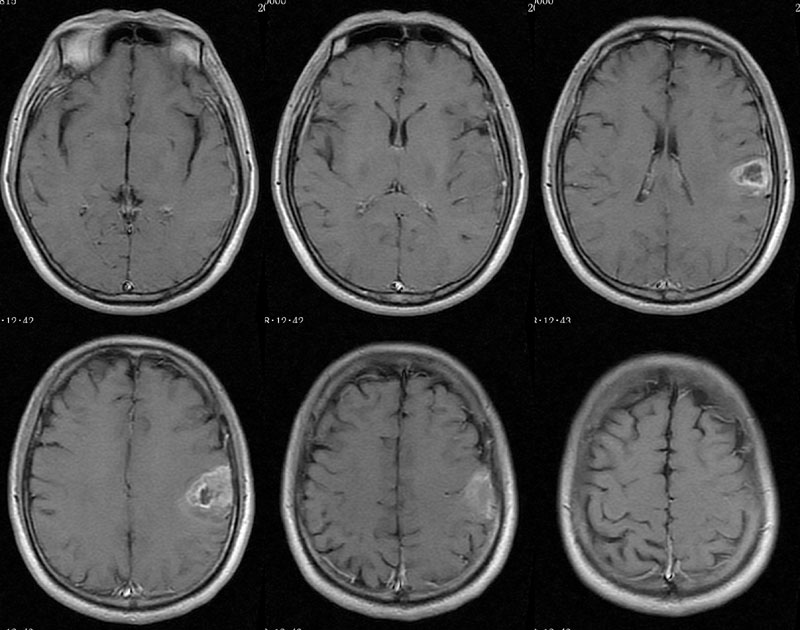

男性,46岁。

主诉:头晕、头痛2月余,加重10天。

现病史:患者2月余前出现头晕,呈天旋地转,阵发性,伴头痛,多于下午发作,伴右侧口角麻木。近10天患者自觉头晕头痛症状加重。

术后病理多形性胶质母细胞瘤 WHO Ⅳ级。

免疫组化:Vimentin(+),GFAP (+),MGMT个别(+),P53约10%(+),Ki67约20%。

考虑胶质瘤可能;中心坏死表现,病变强化比较明显,可以考虑做MRS进一步检查。

CT平扫呈环形稍高密度,MRI呈长T1长T2,信号稍欠均匀,增强扫呈不规则环形强化,邻近脑膜增厚并明显强化。

需要与室管膜瘤相鉴别,脑实质内室管膜瘤很少出现脑膜的强化,钙化较常见。

其次是与转移瘤和淋巴瘤相鉴别。转移瘤常位于灰白质交界区,水肿显著,淋巴瘤常位于中线、基底节、或灰白质交界区,治疗前坏死不常见

左侧顶叶斑片状异常信号,T1低信号,T2高信号,增强后不均匀强化。左侧顶叶多形性胶质母细胞瘤,学习了。